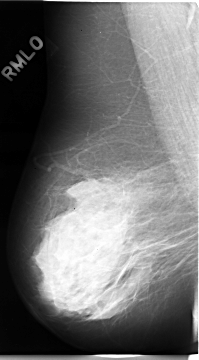

C_0017_1.RIGHT_MLO

RIGHT_CC LINES 4712 PIXELS_PER_LINE 2672 BITS_PER_PIXEL 12 RESOLUTION 50 NON_OVERLAY

RIGHT_MLO LINES 4672 PIXELS_PER_LINE 2584 BITS_PER_PIXEL 12 RESOLUTION 50 NON_OVERLAY